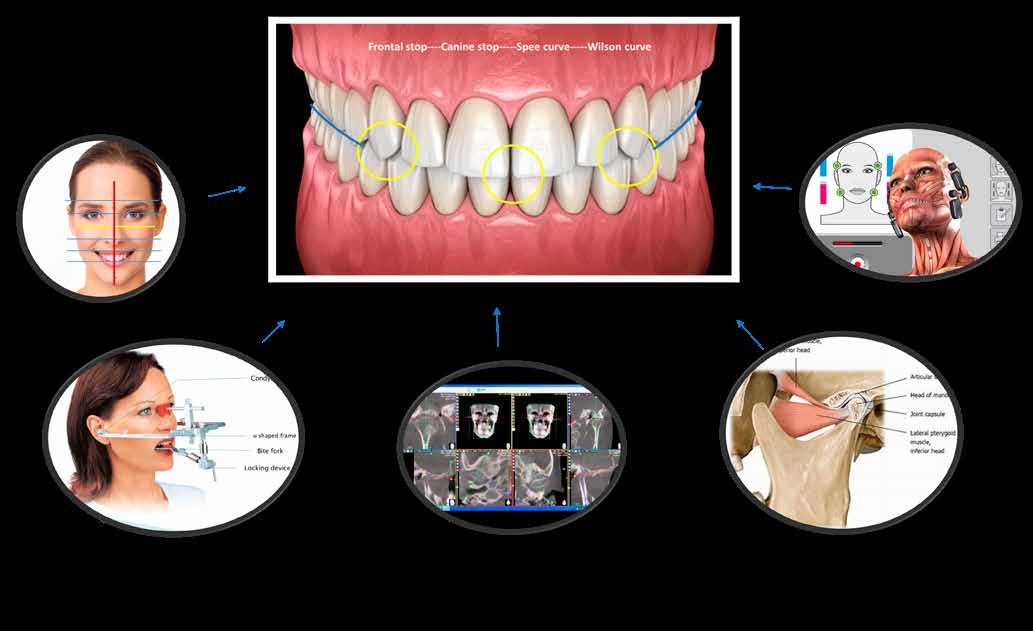

Posselt az állkapocs funkcionális mozgásait a mandibula határmozgásainak görbéjével (Posselt-féle diagram) írta le, amely három térbeli síkra bontható (1. ábra): sagittális, frontális és horizontális. Ebből következik, hogy a fogak dinamikus kölcsönhatása is három dimenzióban értelmezhető [7].

Az egyes csücskök háromdimenzóban végzett, funkcionális mozgáspályáinak összességét nevezzük okkluzális iránytűnek (2. ábra). Az okkluzális iránytű minden csücsök esetében egyedi (a rajta lévő bemélyedések és kiemelkedések szempontjából), és azt a csücsöknek a mandibula condylusának forgásközéppontjához viszonyított helyzete határozza meg.

Az okkluzális iránytű leírásához használt terminológia a The Glossary of Occlusal Terms-ből származik, amelyet a The Glossary Committee of The International Academy of Gnathology állított össze [8]. Fontos megjegyezni, hogy a mandibula mozgásai rágás és nyelés során mindig a maximális interkuszpidációs helyzetből indulnak ki, és oda is térnek vissza.

Ezek a mozgások a következők:

• PROTRUSIO (fekete) – az állkapocs előrefelé irányuló mozgása;

• LATEROTRUSIO (kék) – oldalirányú vagy kifelé történő mozgás;

• LATEROPROTRUSIO (sárga) – kifelé és előre irányuló mozgás kombinációja;

• LATERORESURTRUSIO (piros) – kifelé, hátrafelé és felfelé irányuló mozgás. Ez a mozgás Bennett-mozgásként ismert, Norman G. Bennett (1870–1947) után elnevezve;

• MEDIOTRUSIO (zöld) – mesiális oldalirányú, befelé történő mozgás, amely lehetővé teszi az ellenkező oldali condylus lefelé/előre irányuló mozgását [9].

Az iránytű középpontja (az IKP-ben létrejövő érintkezés) körül található egy kisebb szabad zóna, amely lehetővé teszi az antagonista csücsök mozgását a „hosszú centrikus” (Long Centric vagy Freedom in Centric) tartományban [10]. Ez képezi a Polz-féle biomechanikai wax-up [11] alapját, amelyre a DeVreugd-féle okkluzális iránytű is épül. Jelen publikáció célja egy dinamikus alapú, ésszerű megközelítés bemutatása a hátsó fogak direkt kompozittal történő restaurálásához, amelynek eredményeként a rétegezést követően csupán minimális utólagos korrekcióra van szükség. A szerző a rövidebb, lényegre törő bemutatás kedvéért a felső első molárisra fókuszál. Ezt a fogat azért választotta, mert rágás közben ez viseli a legnagyobb erőbehatást, és ezen a fogon található a legtöbb okklúziós érintkezési pont [9].

DeVreugd-féle okkluzális iránytű.